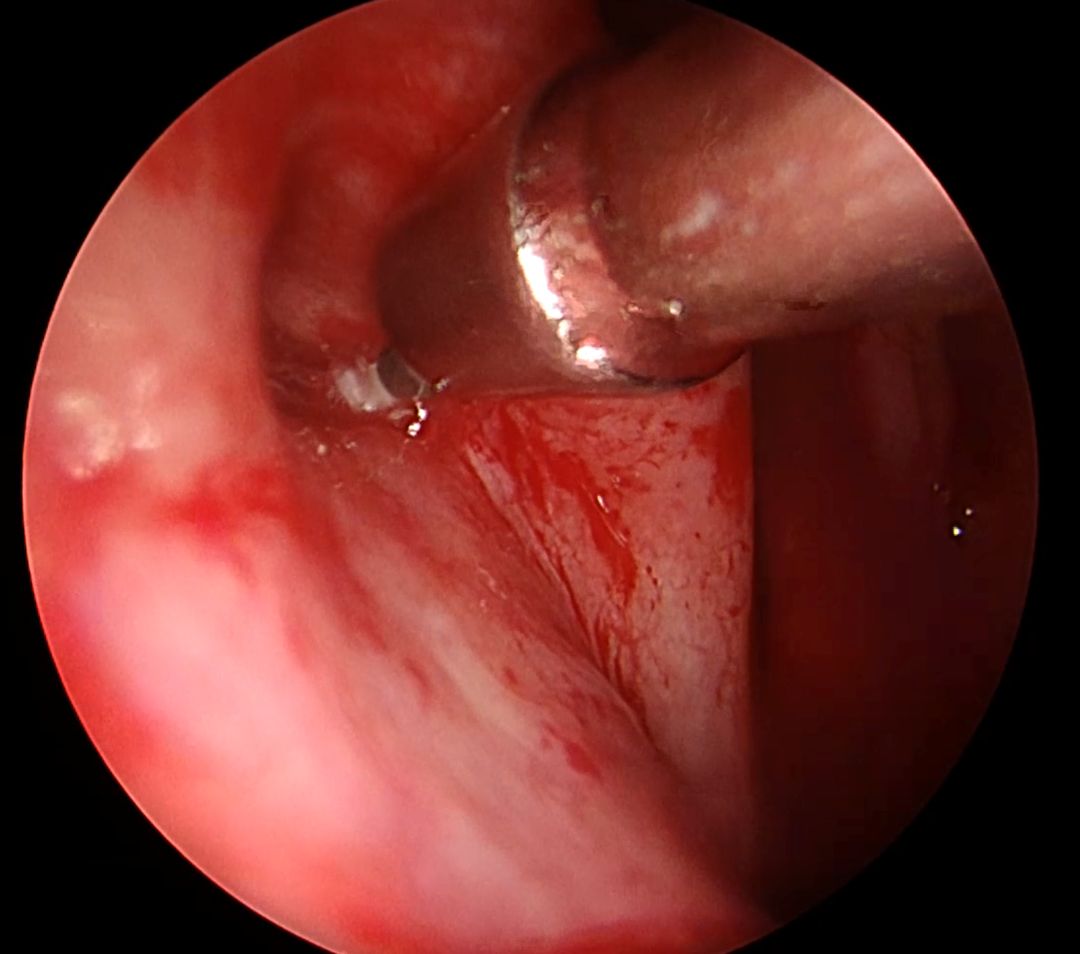

Balonikowanie trąbek słuchowych (trąbek Eustachiusza) to innowacyjna, małoinwazyjna metoda terapeutyczna stosowana u pacjentów z ich przewlekłą dysfunkcją. Schorzenie to może objawiać się uczuciem pełności w uszach, autofonią, pogorszeniem słuchu, nawracającymi infekcjami oraz trudnościami w wyrównywaniu ciśnienia – szczególnie odczuwalnymi podczas lotów samolotem czy nurkowania. Zabieg polega na wprowadzeniu przez jamę nosową cienkiego cewnika zakończonego balonikiem do ujścia gardłowego trąbki słuchowej, pod kontrolą endoskopową. Następnie balonik jest stopniowo wypełniany solą fizjologiczną, co pod działaniem ciśnienia około 10-12 atmosfer powoduje poszerzenie i przywrócenie drożności. Po krótkim czasie balon zostaje opróżniony i usunięty. Cała procedura wykonywana jest w znieczuleniu ogólnym i nie wymaga wykonywania widocznych nacięć.

Procedurę wykonała dr n. med. Marta Kwiatkowska, specjalizująca się m. in. w endoskopowej chirurgii ucha środkowego i zatok przynosowych.